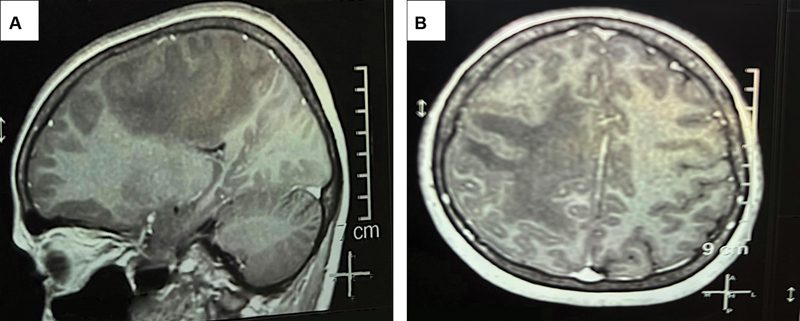

Angiosarcoma of the central nervous system (CNS) is an exceptionally rare and aggressive vascular malignancy presenting significant diagnostic and therapeutic challenges. We report the case of a 22-year-old female with CNS angiosarcoma, highlighting diagnostic intricacies, therapeutic approaches, and management outcomes. Initial symptoms included headache and dizziness, with magnetic resonance imaging revealing a space-occupying lesion in the right parietal lobe, initially misinterpreted as cavernoma. Subsequent surgical resection confirmed angiosarcoma histologically, supported by immunohistochemical analysis showing endothelial markers. Treatment comprised local irradiation postoperatively, resulting in no recurrence or metastasis. Histopathological examination revealed an infiltrative growth pattern with atypical endothelial cells forming irregular vascular spaces. Challenges in diagnosis arise due to overlapping features with other intracranial lesions. Multimodal treatment approaches involving surgery, radiation, and chemotherapy were employed, although their efficacy remains uncertain. Prognosis remains poor, underscoring the imperative for collaborative efforts to enhance understanding and management of this rare malignancy. Our case contributes valuable insights to the limited literature on CNS angiosarcoma, emphasizing the need for comprehensive case studies to refine diagnostic and therapeutic strategies.